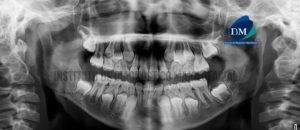

Paciente de sexo masculino de 54 años acude al Instituto de Diagnóstico Maxilofacial para evaluación del sector dentario posterior. A la evaluación de la radiografía